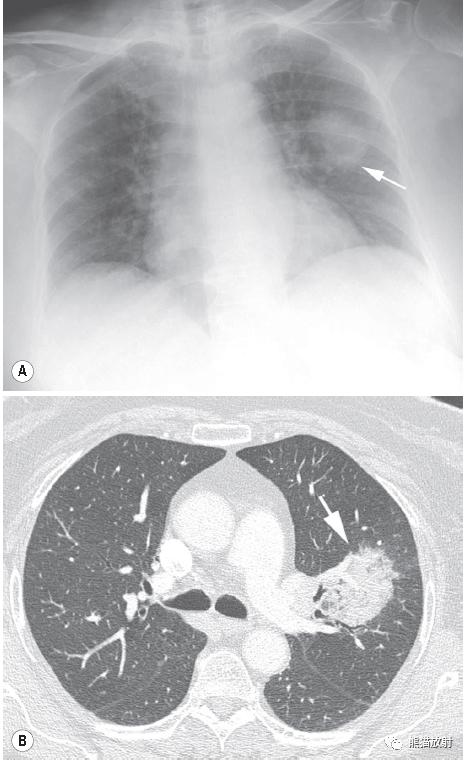

↑ 球形肺炎 Round pneumonia

64岁男性,发热、咳嗽、咳痰。X线平片示左肺上叶肿块样实变;CT示左肺上叶边界清楚高密度影,内含小范围低密度区。痰革兰染色提示肺炎链球菌。